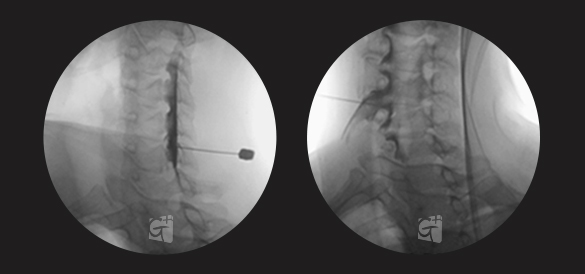

경추 신경성형술

경추 좌측 2번 신경절

경막외 카테터 삽입 -

척추관 안쪽으로 진입하여 약물 주입

원인부위 염증 제거 및 유착 박리

유착박리로 추간공 확보 신경 압박 감소

척추관에서 약물이 퍼져나오는 모습

목 신경 전체를 효과적으로 치료